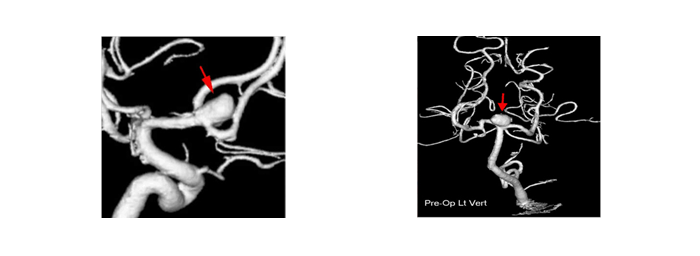

45세 남자환자로 평소 경미한 고혈압 이외에 특별한 증상이 없이 건강하게 지냈는데, 뇌혈관 건강검진에서 아직 터지지 않은 뇌동맥류를 발견하여 사전에 혈관풍선을 GDC-coil을 이용하여 터지지 않게 막아 버린 경우로 미래에 닥칠 수 있는 위중한 뇌출혈로부터 벗어난 경우로 대개 더 이상의 뇌출혈 위험은 없다.

증례 - 사진, 일러스트